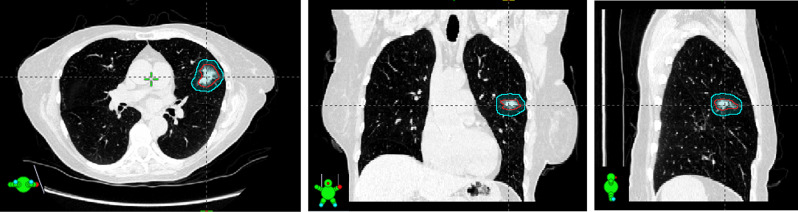

Case presentation: The patient presented with a 2.4 cm spiculated nodule in the left upper lobe (LUL) diagnosed as stage 1A3 lung adenocarcinoma. She declined surgery, and local radiation oncologists deemed SBRT unsafe due to her tremors. Our team proposed a direct-to-unit, single-visit SBRT treatment utilizing anesthesia for immobilization and the Ethos platform for online adaptation to day-of-treatment positioning. An initial treatment plan was generated offline using a diagnostic CT acquired near the patient's home. On the treatment day the patient was anesthetized and a custom foam mold created using a diagnostic CT was used for setup. An internal gross tumor volume (iGTV) was adjusted based on the CBCT of the treatment day. An adaptive plan improved target coverage by 5% without violating organ-at-risk constraints. The entire procedure from initial CBCT to treatment completion took 63 min. Post-treatment recalculations on a CBCT confirmed dosimetric accuracy.